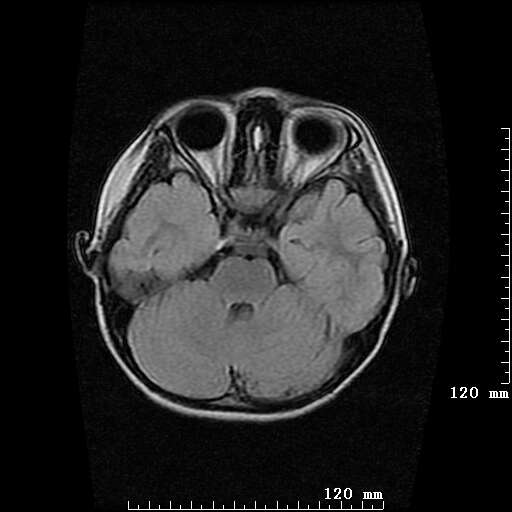

女,7岁,三岁才说话、走路。现智力尚可,走路不稳。临床怀疑大脑发育不全。

考虑 脑白质发育不良

脑折质变薄,双侧侧脑室稍扩张,支持考虑脑折质发育不良

侧脑室周围白质软化症。

考虑胼胝体发育不全,髓鞘形成不良。

支持考虑胼胝体发育不全,髓鞘形成不良。

脑裂畸形伴灰质异位

侧脑室周围白质数量减少,侧脑室不对称性扩大,左侧侧脑室后角呈方形改变,脑沟加深,结合临床考虑脑室周围白质软化症(pvl)。期待结果!

只看出灰质异位

支持脑白质发育不良。